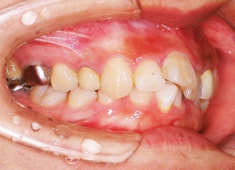

治療開始時